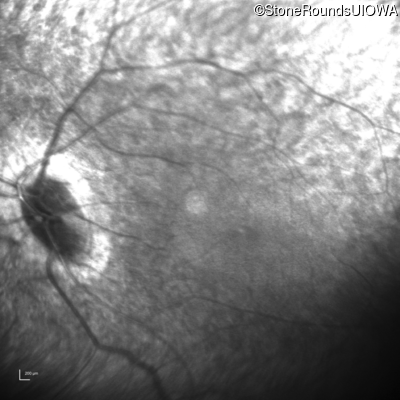

Infrared Fundus Photograph - Left - Light Perception

Exemplar